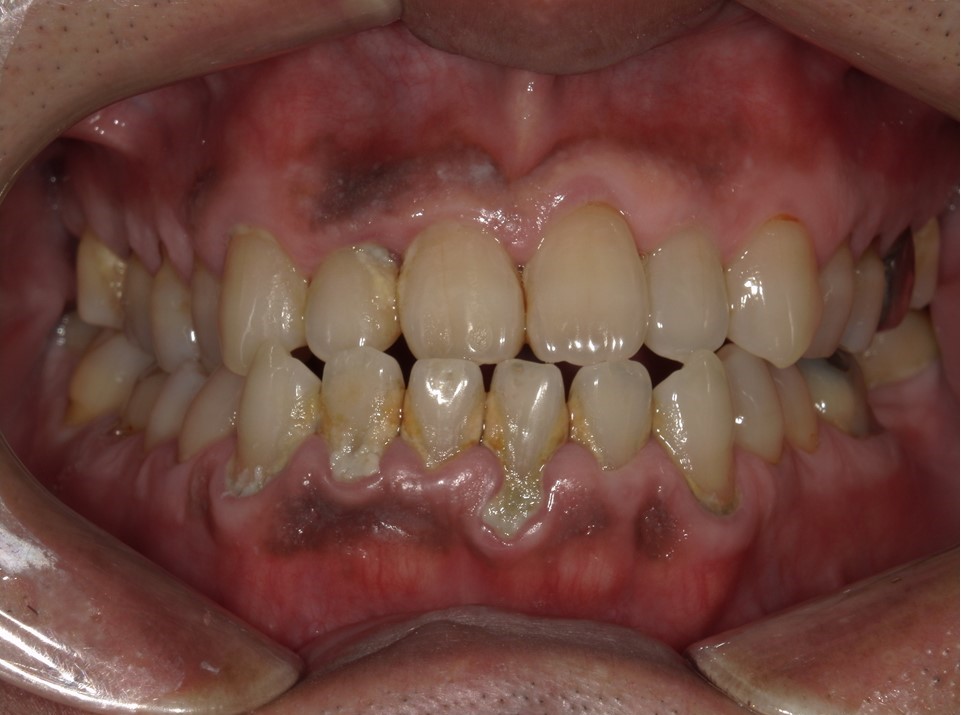

この方はもう10数年ぶりくらいに歯医者に来られた方で、歯石という石灰化して硬くなってしまった汚れがたくさんついて歯茎も腫れ、歯茎から出血しやすい状態でした。

当院では初診時に口腔内写真を撮影させていただいているので、この写真をご本人にもお見せし、現状を理解していただいた上でクリーニングをしていくこととなりました。